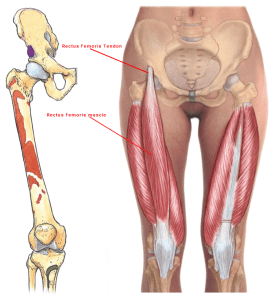

Rectus Femoris

The rectus femoris muscle is one of the four quadriceps muscles that sits in the middle of the front of the thigh.

The rectus femoris attaches from the pelvis to just below the knee (on the patellar tendon.) It is responsible for knee extension and hip flexion.

The other muscles of the quadriceps include the vastus medialis, the vastus intermedius and the vastus lateralis.

It is one of the muscles that make up the hip flexors; a group of muscles that bring the legs and trunk together in a flexion movement.

| ORIGIN Straight head: anterior inferior iliac spine. Reflected head: ilium above acetabulum |

| INSERTION Quadriceps tendon to patella , via ligamentum patellae into tubercle of tibia |